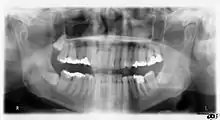

الأشعة السينية للأشعة السينية تنتقل من تكنولوجيا الأفلام (التي تنطوي على عملية التحميض الكيميائي للأفلام) إلى تكنولوجيا الأشعة السينية الرقمية، والتي تعتمد على أجهزة الاستشعار الإلكترونية وأجهزة الكمبيوتر. واحدة من المزايا الرئيسية مقارنة مع النظم القائمة على الأفلام هو مدى التعرض الأكبر. وهذا يعني تقليل عدد عمليات المسح، مما يقلل من التكاليف ويقلل أيضًا من تعرض المريض للإشعاع.يمكن أيضًا إعادة طبع الأشعة السينية عند فقدانها إذا تم حفظ الملف الرقمي. وتشمل المزايا المهمة الأخرى الصور التي يمكن مشاهدتها على الفور، والقدرة على تحسين الصور، والقدرة على إرسال الصور إلى الممارسين والعملاء، وسهولة التعامل مع الوثائق بشكل موثوق، وتقليل التعرض للأشعة السينية، وعدم الحاجة إلى غرفة مظلمة وعدم الحاجة للمواد الكيميائية للتحميض.

تتفوق جودة الصورة بشكل كبير في الأنظمة الرقمية الحديثة المتطورة على الأنظمة التقليدية المعتمدة على الأفلام. كما شهدت أحدث التطورات إضافة تقنية Cone Beam 3D إلى الأجهزة البانورامية الرقمية القياسية.